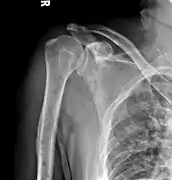

The diagnostic examination of a person with suspected multiple myeloma typically includes a skeletal survey. This is a series of X-rays of the skull, axial skeleton, and proximal long bones. Myeloma activity sometimes appears as "lytic lesions" (with local disappearance of normal bone due to resorption) or as "punched-out lesions" on the skull X-ray ("raindrop skull"). Lesions may also be sclerotic, which is seen as radiodense.[70] Overall, the radiodensity of myeloma is between −30 and 120 Hounsfield units (HU).[71] Magnetic resonance imaging is more sensitive than simple X-rays in the detection of lytic lesions, and may supersede a skeletal survey, especially when vertebral disease is suspected. Occasionally, a CT scan is performed to measure the size of soft-tissue plasmacytomas. Nuclear Medicine Bone scans are typically not of any additional value in the workup of people with myeloma (no new bone formation; lytic lesions not well visualized on nuclear bone scan).

Humerus with multiple myeloma lesions